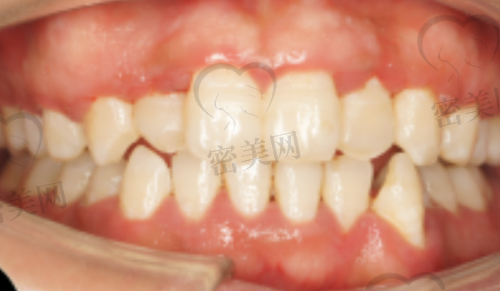

李成呈医生:正畸科医生,主攻隐形矫正、自锁托槽矫正,以治疗方案精细著称。

常规项目包括:牙齿矫正(隐形/金属托槽)、牙齿种植、美白洗牙、微创拔牙、儿童蛀牙治疗、全瓷冠修复、根管治疗、牙周治疗等。